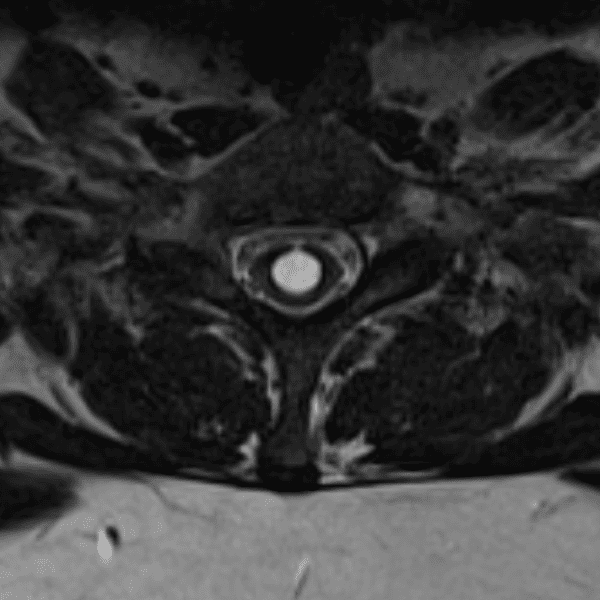

Simulates call by including subtle or difficult cases and some normals.

35 cases